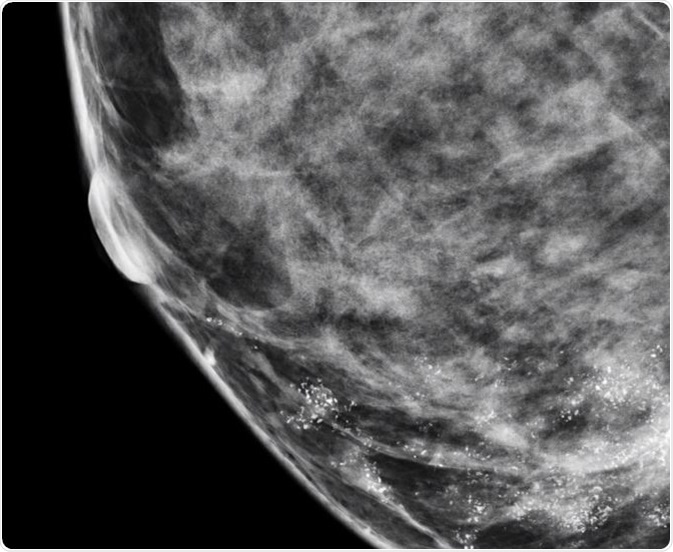

Microcalcifications in Breast

Microcalcifications are actually calcium deposits and are seen as tiny, white dots on a mammogram. They are much less common and are mostly a result of mutations in the breast tissue, though they can be caused by other factors. The appearance of microcalcifications is widely used in the detection of breast cancer at an early stage and can lead to better outcomes.

Nearly 50% of non-palpable cancers in the breast are detected only by the presence of microcalcifications on a mammogram, and approximately 93% of people with ductal carcinoma in situ (DCIS) also present with microcalcifications. Microcalcifications in the breast are very common in women and some studies have observed significant variations in the elemental composition of benign and malignant calcifications.